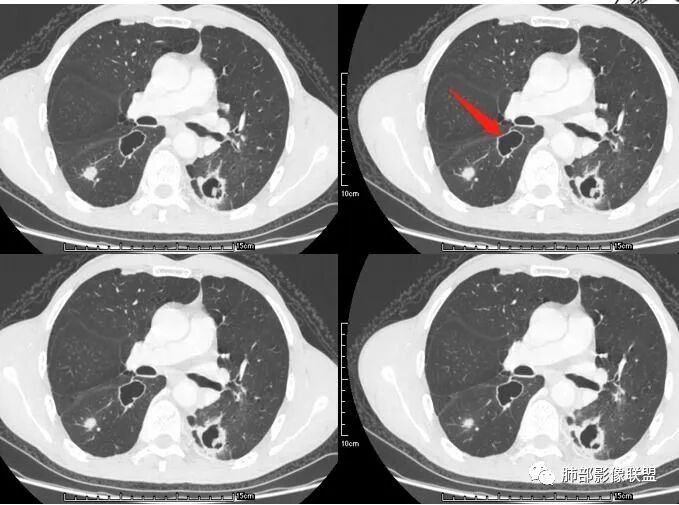

患者老年男性,咳嗽、咳痰、痰中带血伴胸闷2月余。长期大量吸烟史。查肝肾功能、血糖、血脂、心肌酶、电解质、血沉、C反应蛋白、抗“O”、类风湿因子、抗核抗体谱无明显异常。肿瘤标志物提示NSE、CYFRA21-1稍升高。胸部CT:肺气肿背景,左肺下叶后基底段不规则肿块影,见支气管截断,内见大片状低密度区及部分血管影,增强轻度强化,远端空洞形成。双肺多发不规则实性结节影、见毛刺、胸膜牵拉及血管集束,结节内见空洞形成,部分可见血管影,多位于胸膜下。双肺见多发肺大泡。综合考虑左下肺恶性病变并双肺转移。鳞癌或淋巴瘤可能。鉴别血管炎性病变及真菌感染。

张延军:双肺多发结节,空洞影,后者洞壁厚薄不均匀,部分腔内丝丝落落,呈分叶征,边缘见毛刺影,病灶大部分位于胸膜下,与血管相连,右肺下叶前基底段结节近段支气管截断,远端见空腔。左肺下叶病灶密度不均,背段支气管壁增厚,管腔狭窄。考虑1.双肺下叶占位性病变伴肺内空洞性转移 2.多原发的占位 3.肉芽肿性血管炎代排。

本病例左肺下叶肿块,有深分叶、毛刺、胸膜牵拉凹陷、支气管截断及纵隔内淋巴结肿大等征象,都均支持病灶为恶性,如腺癌,而且叶间裂的多发结节也提示是腺癌来源可能大;双肺多发结节、肿块,大部分病灶有分叶、毛刺及胸膜凹陷的恶性征象,与原发肿瘤本身的性质有关,所以应该与左肺下叶肿块同源,而且双肺多发病灶内空洞也具有多样性;

此病例中空洞形态多样,内壁不光整,有分隔影,周围未见明显卫星灶及钙化灶,结核不太符合;患者病史慢性病史,无明显发热,缺乏中毒临床表现,急性感染基本排除;各种中性粒细胞胞浆抗体阴性,没有鼻窦炎,肾脏等病史,基本排除血管炎;霉菌性空洞常见于免疫机能低下者, 常为空洞、肺炎、伴“ 晕圈”征的结节及支气管扩张合并存在。